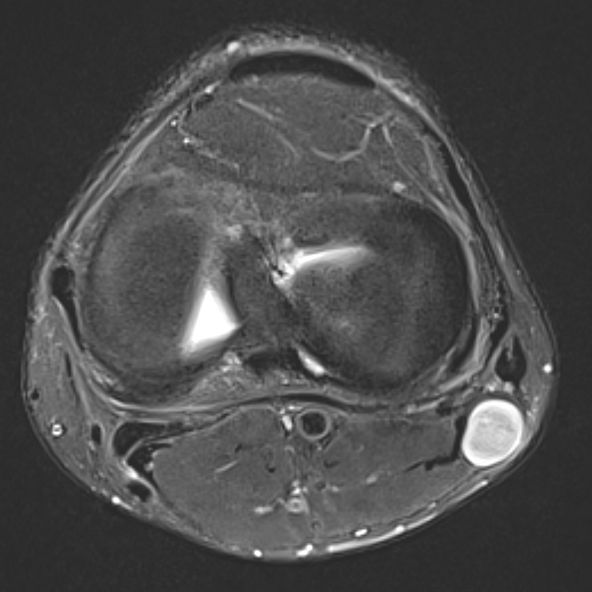

MRI

Target sign

- hypointense centrally

- hyperintense peripherally